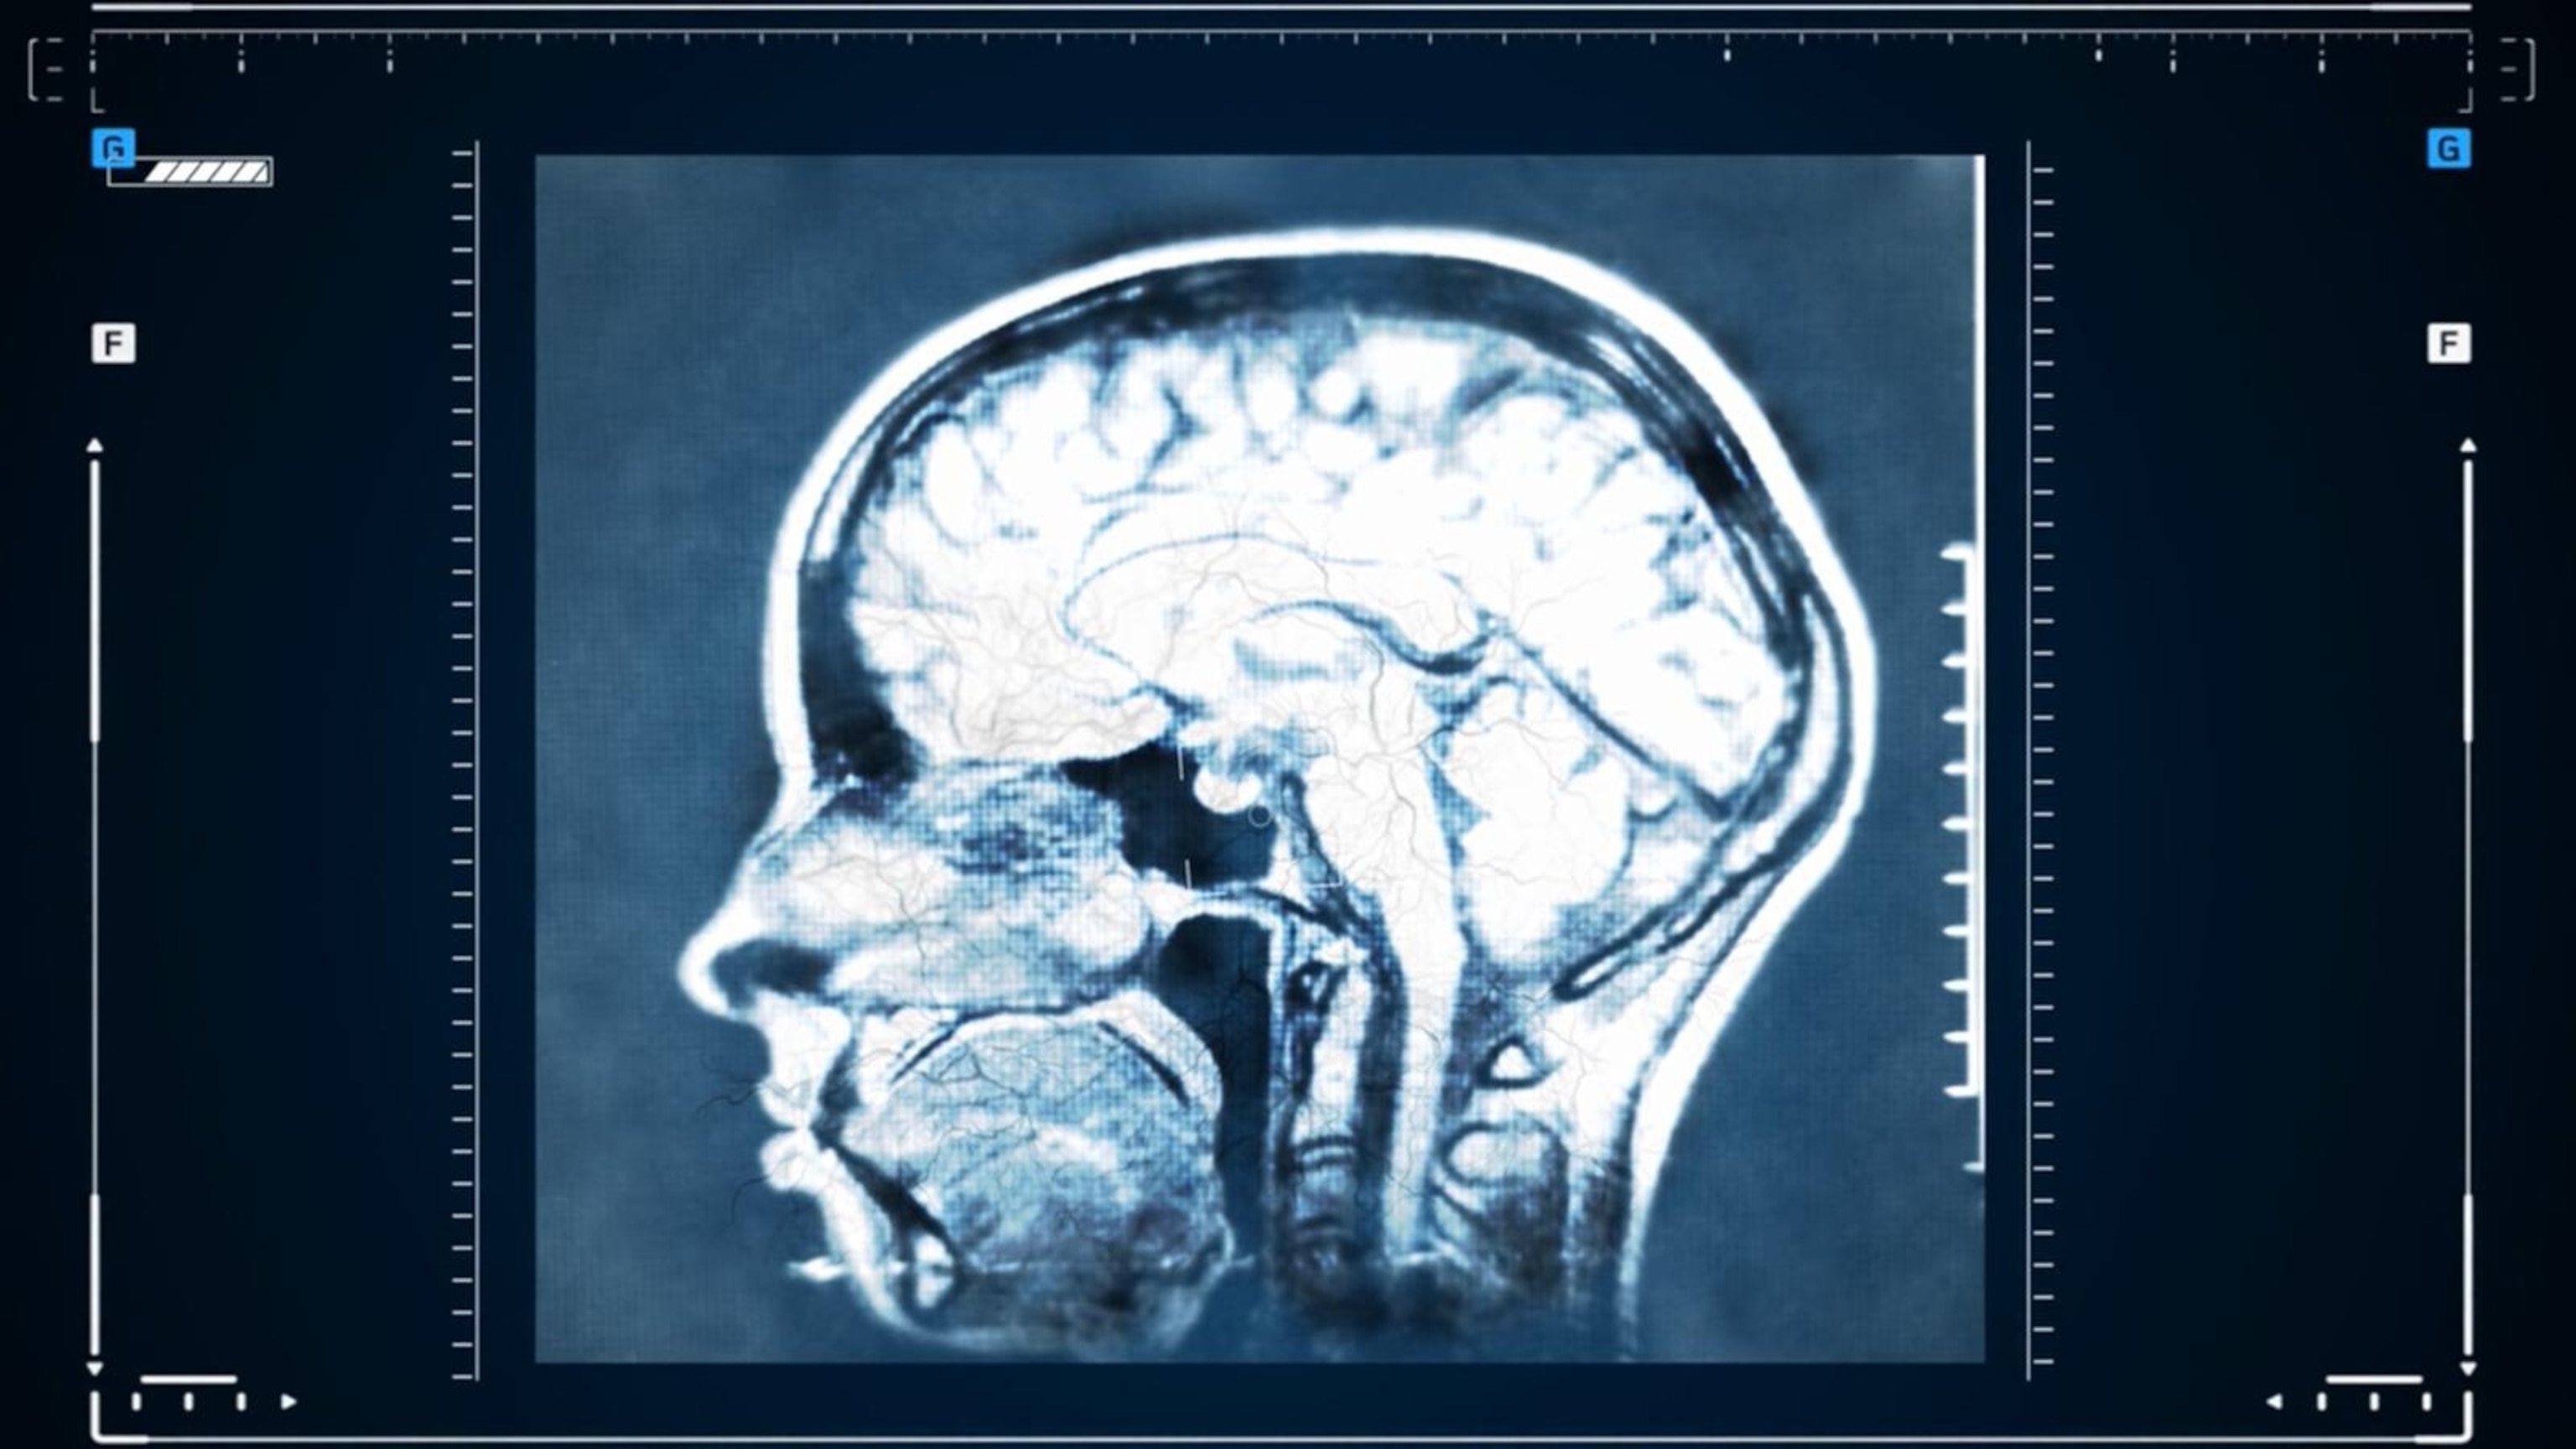

The University of Hawaii's landmark 11-year longitudinal study published in Neurology, analyzing 93,000 multiethnic participants (mean age 59, 55% women) from Hawaii and California, reveals a critical consumer insight: diet quality—not dietary category—drives health outcomes and purchasing decisions. The research distinguished between healthful plant-based diets (whole grains, legumes, vegetables, fruits, nuts) and unhealthful variants (refined grains, added sugars, ultra-processed foods), finding that highest-quintile consumption of quality plant foods reduced Alzheimer's disease and related dementias (ADRD) risk by 7% (HR 0.93), while unhealthful plant-based diets increased risk by 6% (HR 1.06). Critically, participants who shifted toward healthier patterns demonstrated 11% lower risk, while those moving toward unhealthier options faced 25% higher risk—a 36-percentage-point swing that signals powerful consumer behavior change potential.